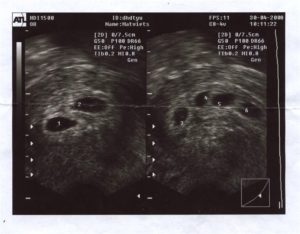

Двойня на УЗИ

В 25% случаев из 60% удачных результатов ЭКО развивается многоплодие. Это случается по причине того, что женщине подсаживают сразу несколько эмбрионов для увеличения шансов на беременность. Иногда один зародыш не приживается, а второй успешно имплантирует и продолжает развитие.

Часто приживаются все, и тогда, по желанию родителей, врачи могут изъять лишние эмбрионы. Но сделать это необходимо на самых ранних сроках, поэтому точное определение количества эмбрионов так важно. Узнать точное количество возможно только с помощью ультразвукового обследования.

Нормальными показателями размеров зародыша принято считать:

- Внутренний диаметр плода равен 18–22 мм.

- Копчико-теменной размер зародыша достигает 3–6 мм. Данные актуальны на 28 день после подсаживания клетки.

- Желточный мешочек должен равняться 3 мм в диаметре.

Сведения не дают на 100% корректную картину, поскольку зависят от дня имплантации эмбриона. Обычно для наступления беременности необходимо 3–10 дней, в зависимости от подготовки среды в матке на день переноса зародышей. Сроки внедрения эмбрионов в матку еще зависят от дня продолжительности жизни бластоцисты. Обычно пятидневки быстрее имплантируют, чем трехдневки.